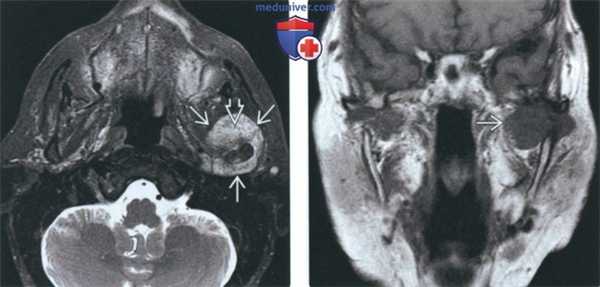

(Слева) На аксиальной МРТ (Т2ВИ FS) у пациента с ХС левого ВНЧС определяется мягкотканный компонент с неоднородным, но в целом высокоинтенсивным Т2 сигналом, типичным для хондроидных опухолей. Точечные гипоинтенсивные очаги отражают внутриопухолевые кальцинаты.

(Справа) На корональной МРТ (Т1ВИС+ FS) у этого же пациента определяется интенсивное накопление контраста в объемном образовании сустава, что подтверждает его солидную структуру и позволяет исключить жидкость в суставе, растягивающую капсулу.